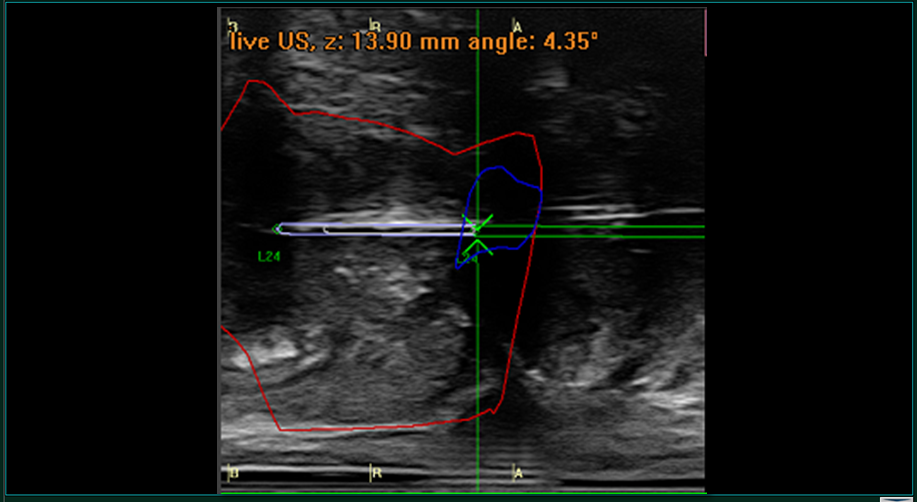

–Εν συνεχεία τοποθετείται το ειδικό υπερηχογράφημα στο ορθό (έντερο) και απεικονίζεται σε πραγματικό χρόνο ο προστάτης και γίνεται η σύντηξη των εικόνων της μαγνητικής με αυτές του υπερήχου. Παράλληλα σχεδιάζονται και προγραμματίζονται τα δείγματα που θα ληφθούν ώστε οι βιοψίες να είναι στοχευμένες και με μεγάλη ακρίβεια να εξασφαλισθεί η λήψη βιοψιών από τις ύποπτες περιοχές. (Βλέπε Εικόνα 7)

-Εν συνεχεία λαμβάνονται τα δείγματα των βιοψιών. Για την λήψη των δειγμάτων με ακρίβεια χιλιοστού στο περίνεο εξωτερικά τοποθετείται ειδικός πίνακας συντεταγμένων (Αγγλική Ονομασία Grid).Ο πίνακας αυτός είναι σε πλήρη συμφωνία με το λογισμικό και την σχεδίαση του προστάτη και των βλαβών με αποτέλεσμα ο Ουρολόγος να τοποθετεί την βελόνα λήψης βιοψιών με βάση τις οδηγίες του λογισμικού σε συγκεκριμένο σημείο που ανταποκρίνεται στην πράξη ακριβώς σε αυτό το σημείο του προστάτη στο σώμα του ασθενή.(Βλέπε Εικόνες 8 & 9) (Βίντεο 1)

Βίντεο 1: Δείτε την στοχευμένη λήψη βιοψίας με βάση τις κατευθύνσεις του λογισμικού BiopSee.Ο ουρολόγος της ομάδας μας έχοντας ήδη σχεδιάσει τον προστάτη και την βλάβη στοχεύει στην βλάβη [F-10] τοποθετώντας την βελόνα στον πίνακα συντεταγμένων λαμβάνοντας με εξαιρετική ακρίβεια από το ζητούμενο σημείο.

-Δείγματα λαμβάνονται ξεχωριστά από κάθε ύποπτη περιοχή και αποστέλλονται ξεχωριστά στον παθολογοανατόμο με πλήρης περιγραφή των ευρημάτων της μαγνητικής για την συγκεκριμένη βλάβη και βέβαια την περιοχή λήψης του προστάτη από όπου προέρχεται.Το πλήθος των βιοψιών εξαρτάται από το μέγεθος της βλάβης καθώς και του προστάτη.(Βλ.Εικόνα 10)

Εικόνα 10: Δείγμα βιοψίας όπως φαίνεται στο υπέρηχο την στιγμή που την λαμβάνει ο ουρολόγος.Με κόκκινο είναι το περίγραμμα του προστάτη, με μπλε είναι το περίγραμμα της ύποπτης περιοχής και η βιοψία απεικονίζεται με τις πράσινες οριζόντιες γραμμές που είναι η βελόνα του ουρολόγου.Με τον τρόπο αυτό ο Ουρολόγος βλέπει σε πραγματικό χρόνο και γνωρίζει με ακρίβεια χιλιοστού από που λαμβάνει τις βιοψίες.